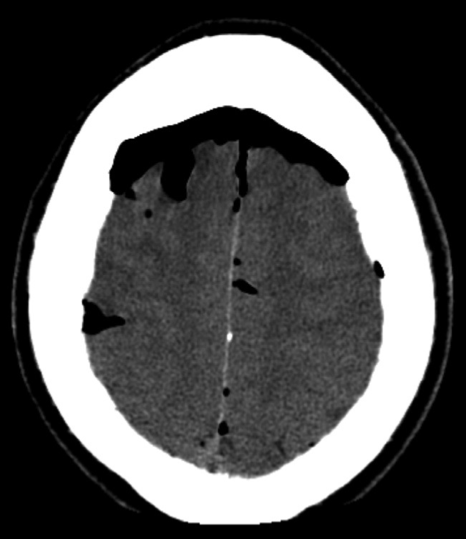

If there is a penetrating skull injury or a fracture involves the normally pneumatized paranasal sinuses, middle ears or mastoids, air may enter the cranium and be seen on CT as locules of very low density gas. CT can also demonstrate fluid (blood) in the sinuses and mastoid air cells or air in the orbits, suggesting a facial or skull base fracture.

CT scan showing low density air in the sulci of the brain from a basal skull fracture involving the sinuses.